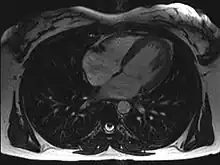

![]() An MRI of a 13 year old female's heart beating. | |